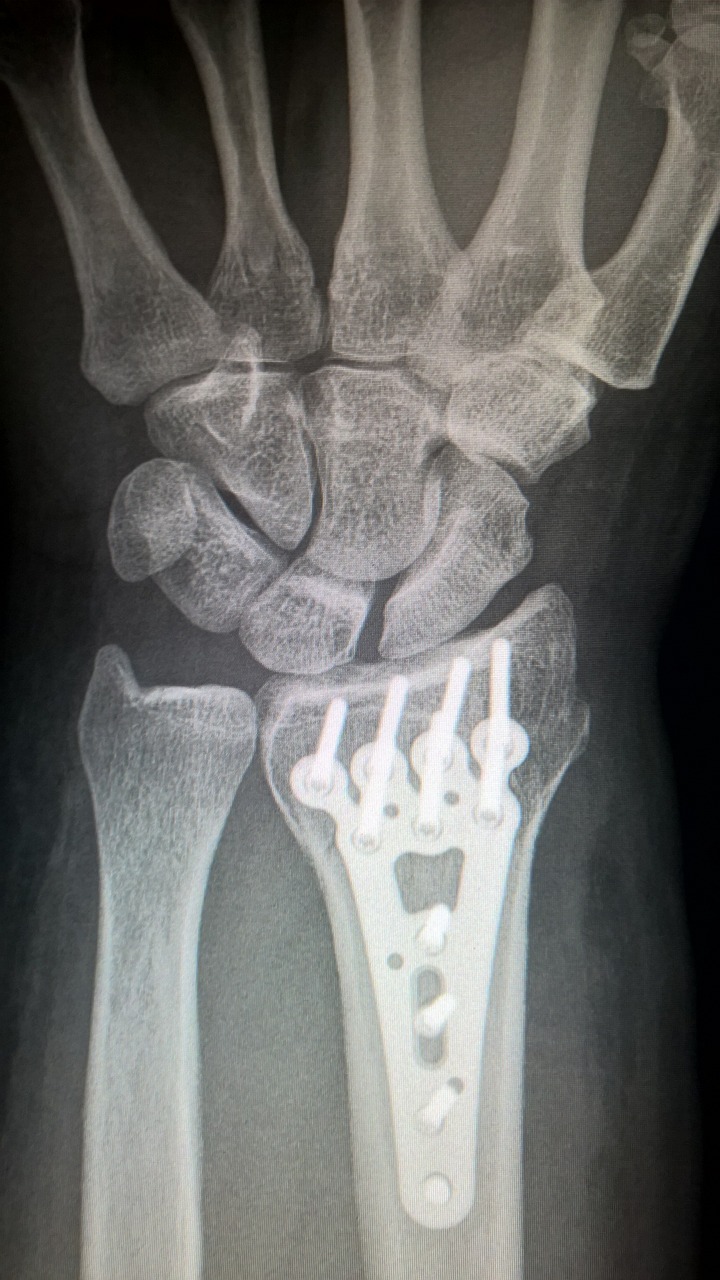

특히 무릎, 손목, 허리 등 다양한 부위의 관절 통증 관리에 도움이 돼요.